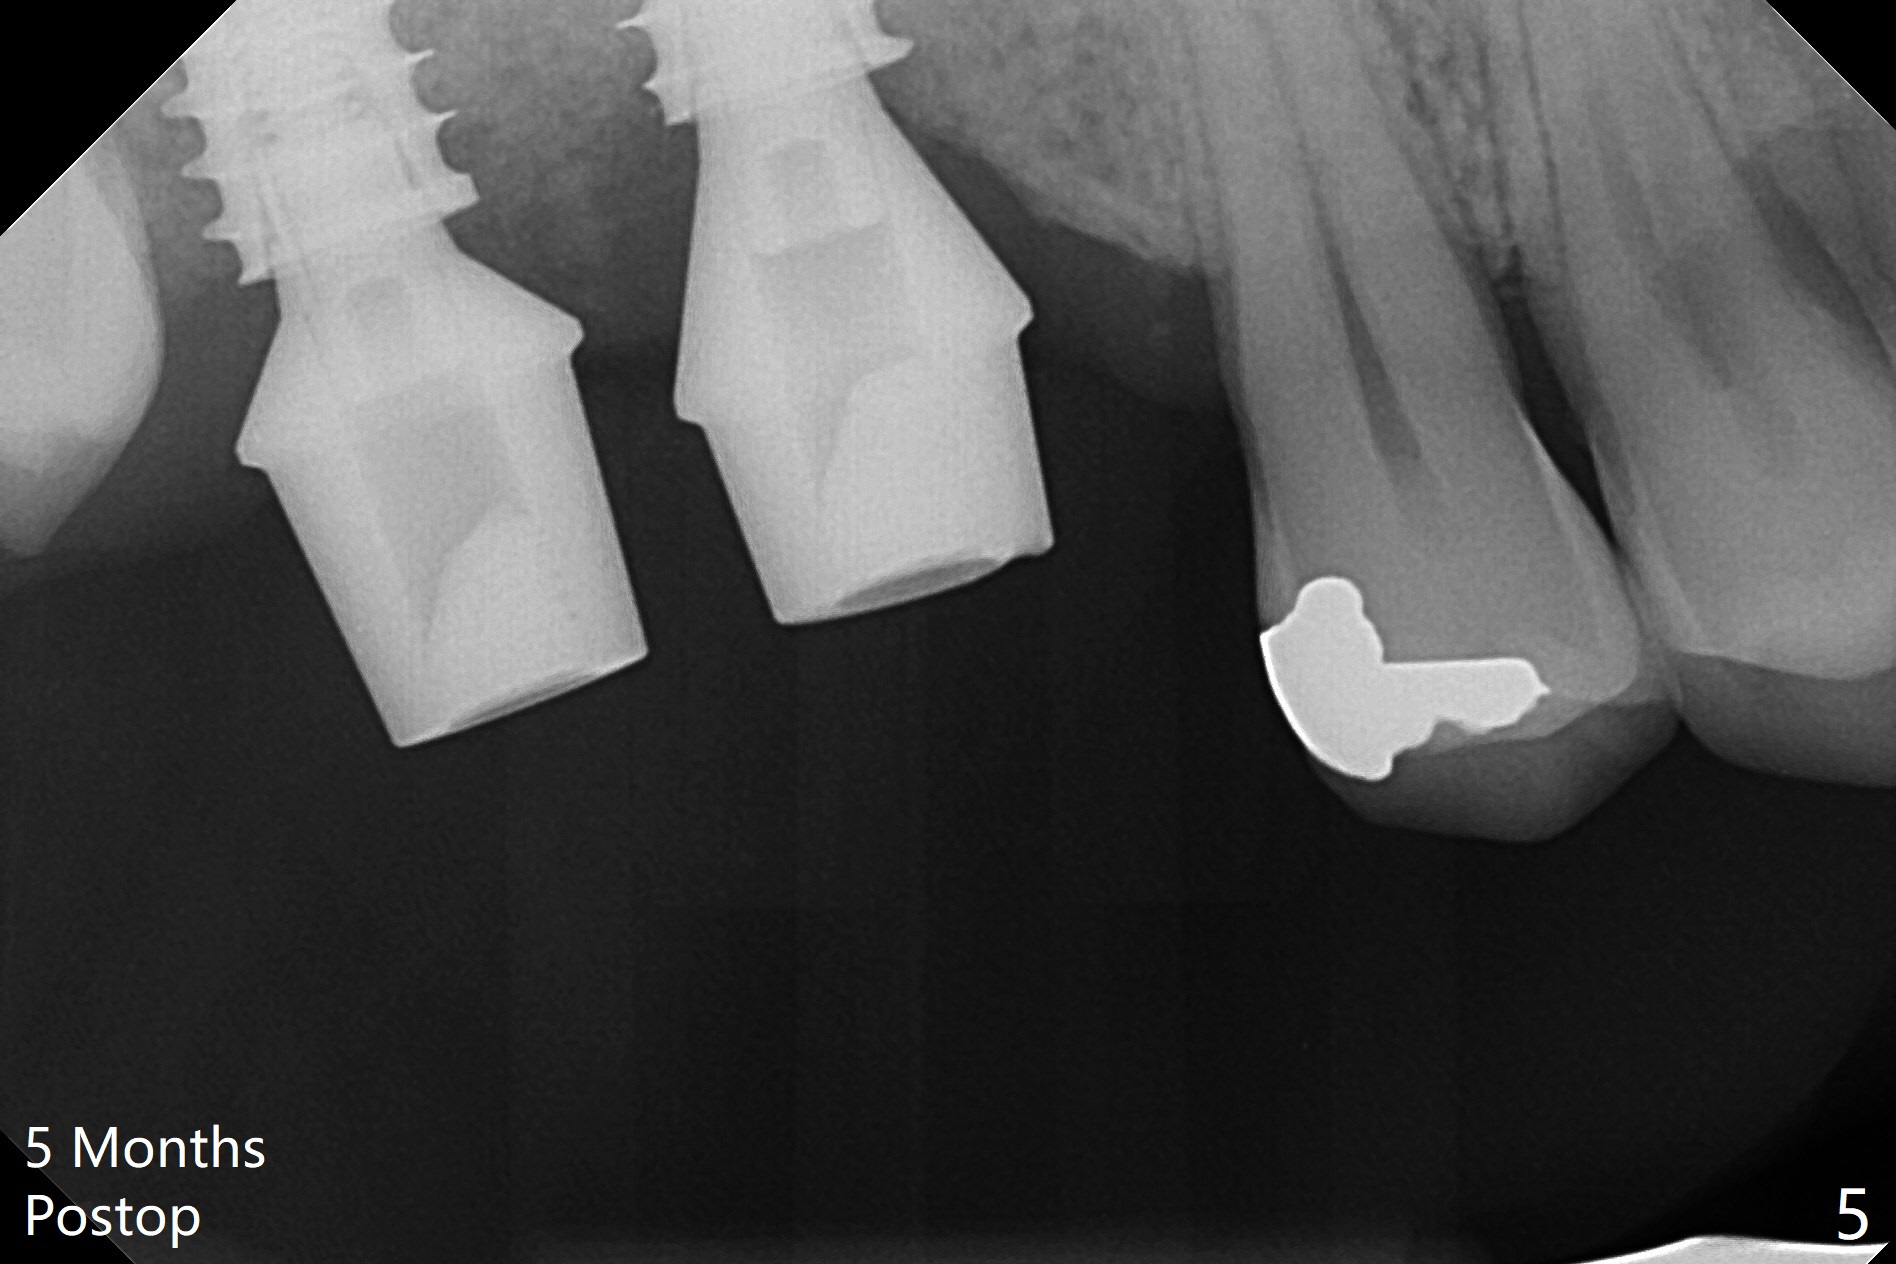

The gingiva at #2 adapts to the abutment 3.5 months post placement (Fig.1). After incision, osteotomy at #3 is initiated by free hand, which is found off (Fig.2 (red line: normal trajectory)). After repositioning osteotomy, a 4.5x11 mm dummy implant is placed with minor trajectory issue (Fig.3). Following further adjustment, a 5x11 mm implant is placed with relatively normal axis; a 6.5x4(4) mm abutment is inserted. Autogenous bone, Vanilla and Osteogen are placed distobuccally (Fig.4). Guided surgery should be more efficient and precise. There is no implant thread exposure 9 and 5 months postop at #2 and 3, respectively (Fig.5,6). The mesial wall of the crown at #2 is thin, having a crack line. The crowns at #2 and 3 are cemented with RelyX Ultimate Adhesive Resin Cement bonding. If the crown fractures, change the abutment (6.5x5.7(2) mm) to the one with smaller diameter (4.5 or 5.0 mm), or trim the abutment mesially heavily. Guided surgery or stent should prevent the potential complication.